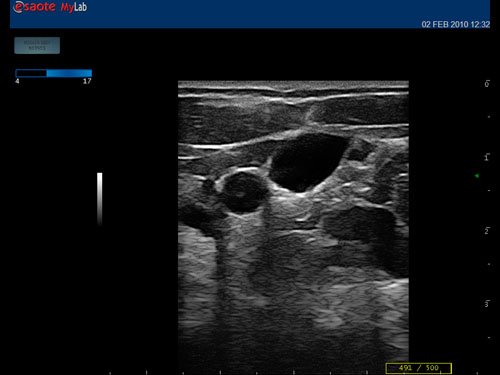

12”-Full-Touchscreen Farbdoppler

Das MyLab™One steht für das revolutionäre „Arm-held“ Hochleistungs-Ultraschallsystem mit 12”-Full-Touchscreen. Aufgrund seines geringen Gewichts und der Tragbarkeit kann es auch ohne Arbeitsfläche verwendet werden. Eine einzelne Person kann dieses Gerät aufgrund seiner einzigartigen Funktionen allein und selbstständig bedienen.

Das Ultraschallsystem MyLab™One zeigt exemplarisch den modernen Bedarf an Diagnosekapazitäten in verschiedenen Anwendungsbereichen: Radiologie, Kardiologie, Phlebologie, Frauenheilkunde, Orthopädie, Regionalanästhesie, Sportmedizin, Interventionell, Rheumatologie, Erste Hilfe, Notfallmedizin, Vaskuläre Reihenuntersuchungen, Allgemeinpraxis.

• Features: Farb/Doppler, Nadelführung, SW/B-Bild